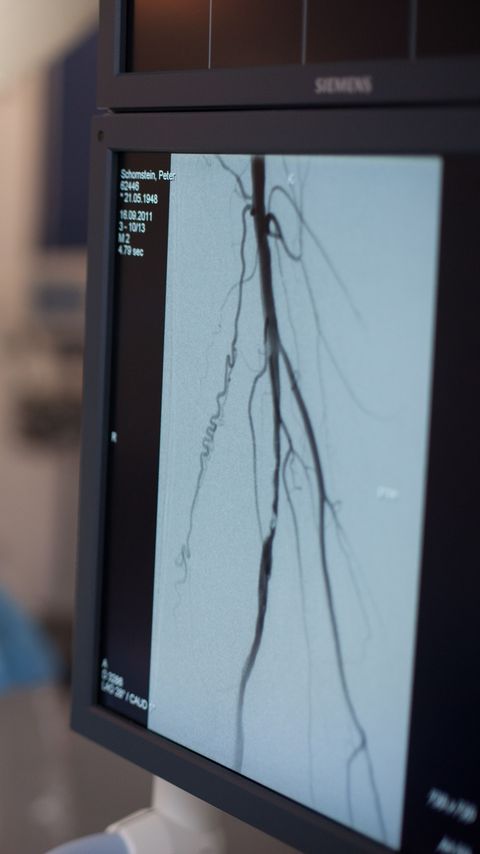

Klinik für Gefäßchirurgie

Gefäßzentrum